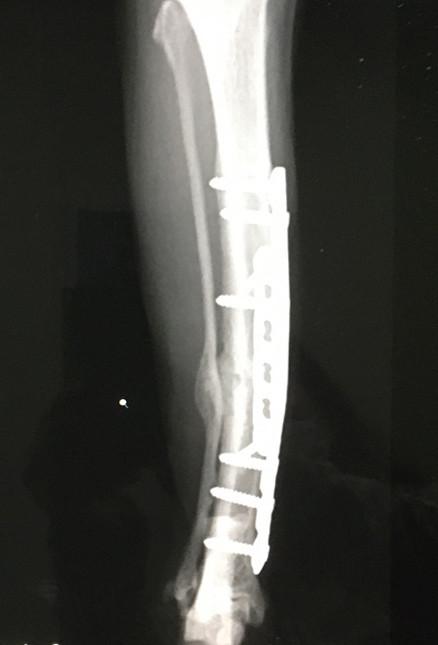

で今回のレントゲン結果

結構骨形成が進んでるー。

意外と運動して血流良くなったのが効果あったのかも!。

ワンコならこの状態でプレート抜去のスケジュールを組むんだけど

なんせプレート曲げた前科のある猫なのと、

今回もレントゲン撮って様子見。

骨形成の経過良好なのでプレート抜去手術のスケジュールを組みました